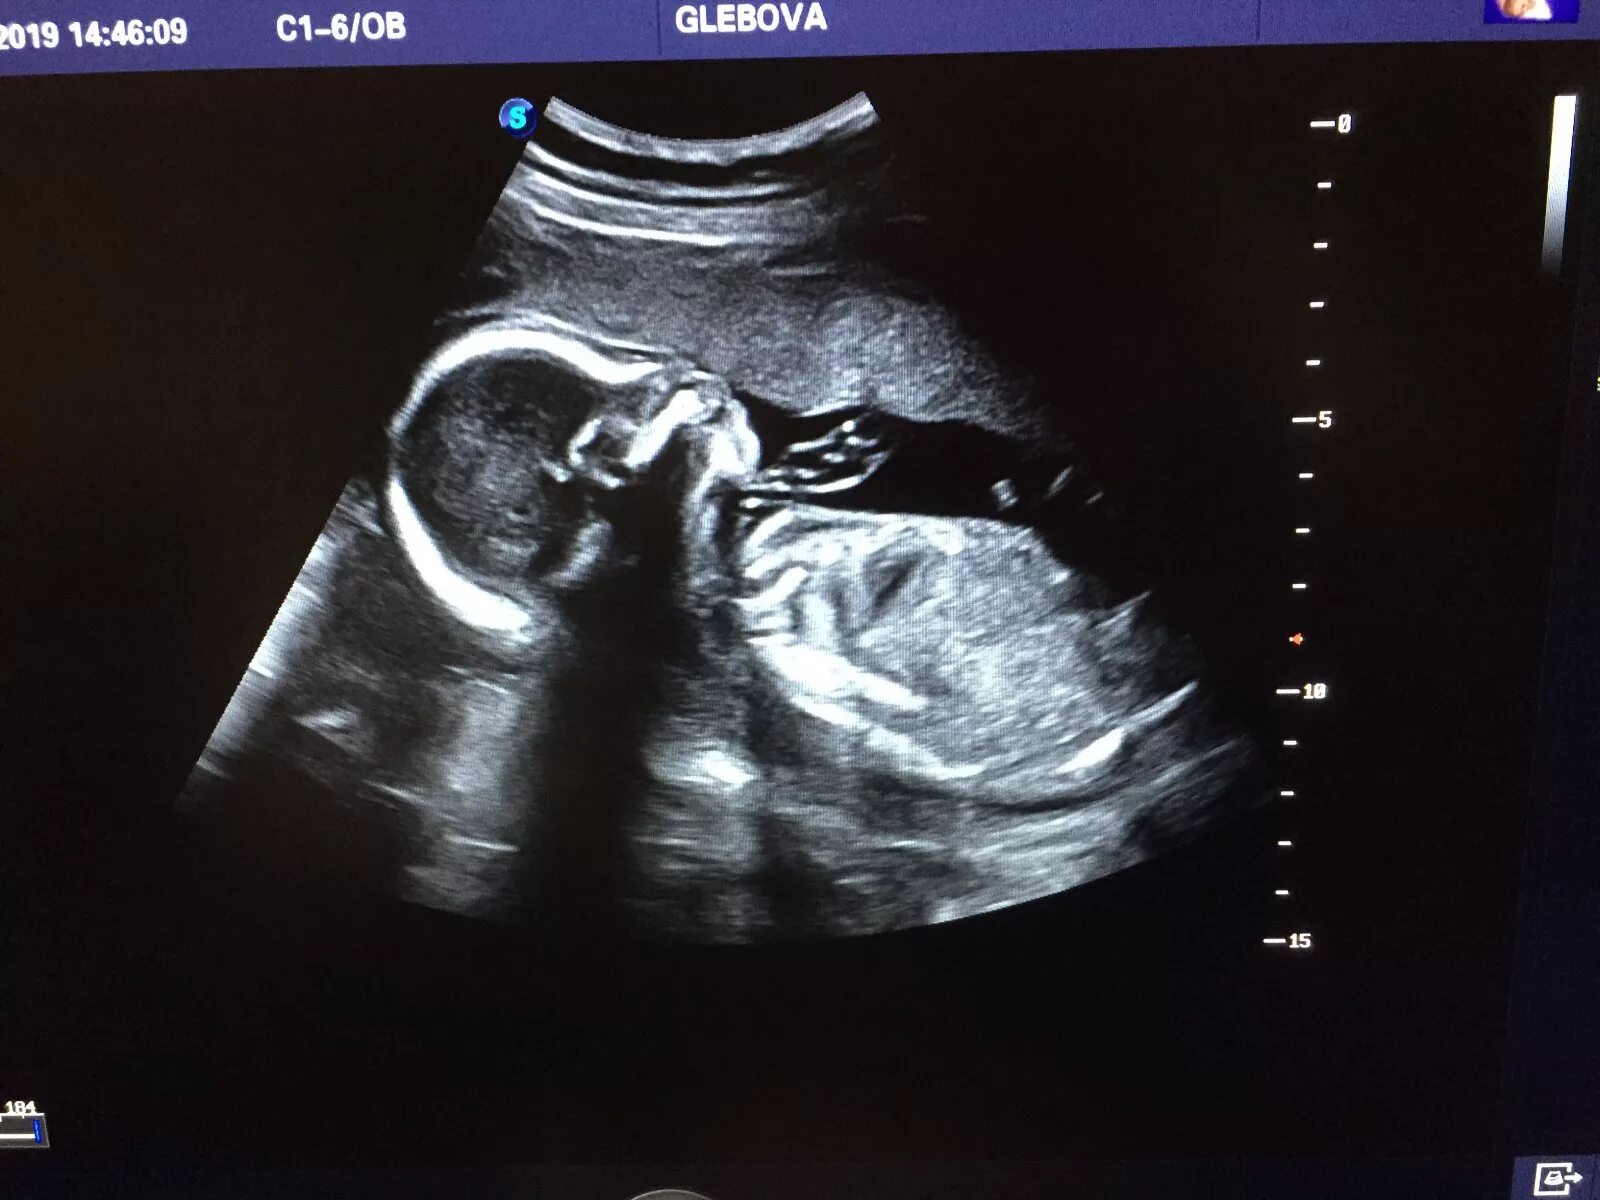

Ви и узи